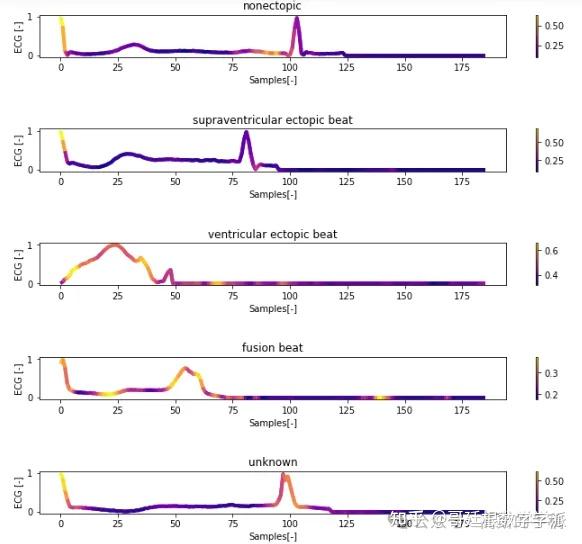

一维神经网络的特征可视化分析-以心电信号为例(Python,Jupyter Notebook)

包括Occlusion sensitivity方法,Saliency map方法,Grad-CAM方法